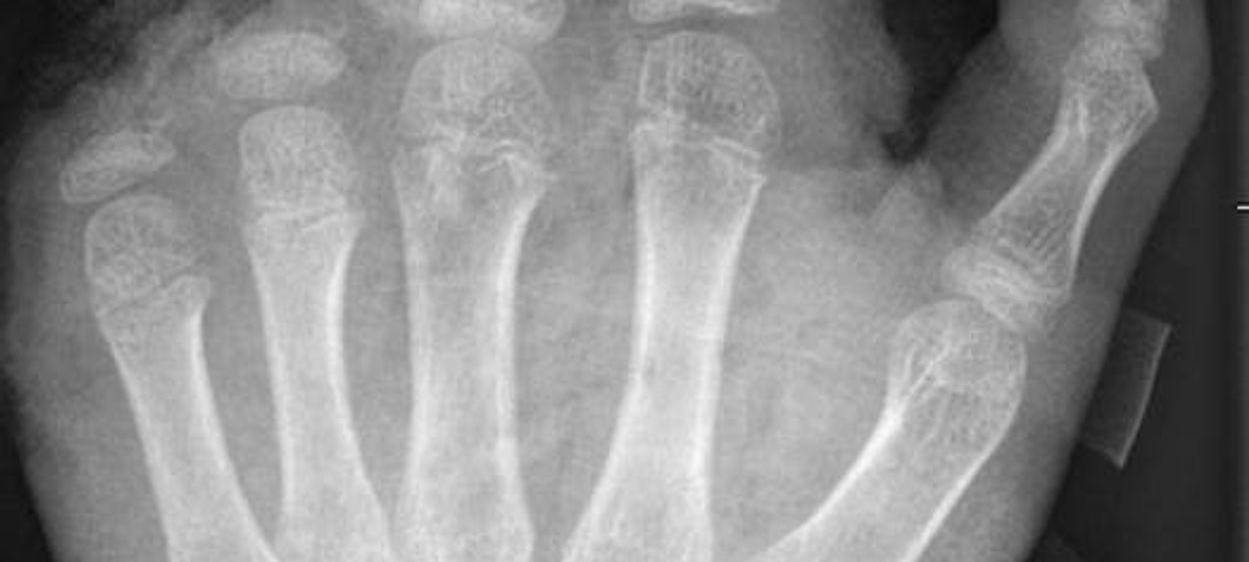

Berlin (dpa) - Abgetrennte Finger, durchtrennte Sehnen, Amputationen - die Handchirurgin Leila Harhaus-Wähner hat in der Silvesternacht schon vieles gesehen. Auch in diesem Jahr rechnet die Berliner Ärztin mit zahlreichen Böller-Verletzten. «Für Handchirurgen ist es klar, dass Silvester die arbeitsreichste Nacht sein kann.» Bis 24 Uhr passiere erstmal nicht so viel, ab 1 Uhr, 2 Uhr nachts kämen immer mehr Verletzte in die Notaufnahme und dann «sehr viele in sehr kurzer Zeit.»

In der Handchirurgie müssten an Silvester im Unfallkrankenhaus rund 20 bis 40 Menschen mit Böllerverletzungen operiert werden, sagt die Ärztin. Dieses Jahr werde sie mir vier weiteren Handchirurgen im Einsatz sein. Die häufigsten Verletzungen entstünden durch explodierende Böller in der Hand.

«Der überwiegende Teil der Verletzungen trägt tatsächlich lebenslange Folgen mit sich, weil die Sprengkraft dazu führt, dass eben nicht nur einzelne Strukturen verletzt sind, sondern immer mehrere. Und das heilt praktisch nie ganz folgenlos ab.» Zum Teil könnten Hände nicht mehr gerettet und müssten amputiert werden.